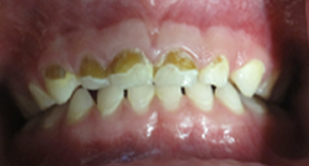

Before Sealant Applied

After Sealant Applied